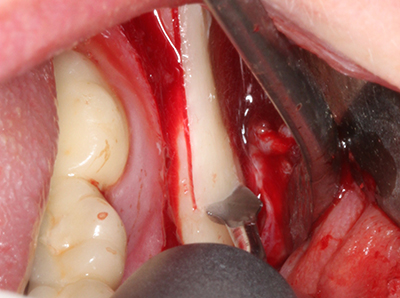

Пиезохирургията има допълнителни предимства при събиране на костни блокове. В допълнение към високата прецизност при остеотомията, описана по-горе, употребата на фините режещи накрайници значително намаляват загубата на материал. Голяма загуба на материал по време на събиране може да се очаква с дебелите накрайници, особено при употреба на борери Линдеман (Lakshmiganthan, Gokulanathan et al. 2012). Базалното разделяне, което е необходимо, особено за присадка на блок при ретромолар, е улеснено от специално създадени правоъгълни триони. В резултат на това, пиезохирургията е разглеждана като прецизна, улеснена и безопасна процедура за събиране на костни блокове в ретромоларното пространство (Happe 2007) (Фиг. 1-12).

Костната тъкан е не само минерализирана структура, тя съдържа и съществено количество колагенови влакна. Това означава, че тя има не само добра компресивна сила, но и известна степен на гъвкавост, която може да се възприеме като предимство при извършване на костна аугментация. В класическата процедура по разширяване чрез костно разделяне, атрофиралият алвеоларен гребен е разделен надлъжно и внимателно разширен след достигане на подходящата остеотомна дълбочина (Фиг. 13-16), в идеалния случай без допълнително отстраняване на периостеума (Brugnami, Caiazzo et al. 2014, Stricker, Fleiner et al. 2014). Системите с винт и пластини с увеличаване на разстоянието при разширяване са доказали ефективността си при разделяне на двете костни ламели, оставайки под прага на фрактурите. В общи линии, оставащата ширина на костта от поне 3–4 mm е задължителна (Chiapasco, Zaniboni et al. 2006), за да се гарантира добра гъвкавост и достатъчно костно покритие за бъдещото поставяне на импланти. Ако е необходимо, вертикалната остеотомия на едната или двете страни може да подобри гъвкавостта. Комбинацията с допълнителни техники за аугментация, особено в букалната страна, е описана като алтернатива на класическата техника.